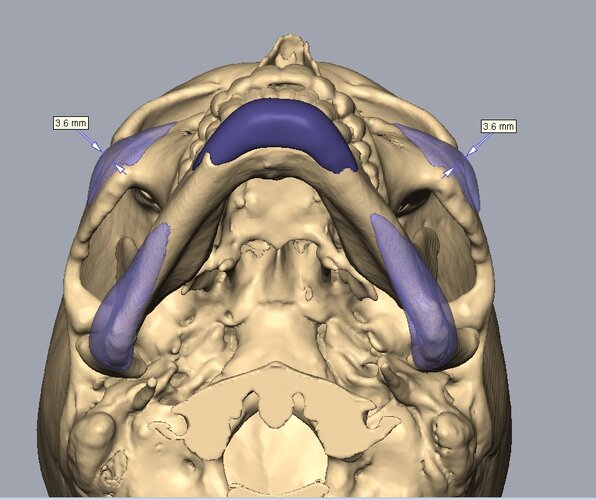

Recieved the draft 1 of the design, what changes should i ask for?? a couple of things i can think of are malar implants not giving enough lateral protrusion, gonion flaring.

I also am planning to include infra implants as well.